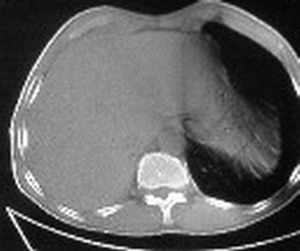

ct值约12hu。

ct值约12hu

右肺下叶支气管闭塞,中间段支气管狭窄,下叶不张,胸腔及叶间积液.中心型肺癌伴下叶肺不张.胸腔和叶间积液.

考虑中心型肺癌伴下叶不张,肺底积液吧。

右肺下野后部均匀低密度影,边缘锐利,前缘外突(不支持肺不张),纵隔内未见明显肿大淋巴结,右下肺门结构显示欠清,临床资料太过简单,考虑右侧后胸部包裹性积液。其他待排。建议密切结合临床其他检查。

ct值12,包裹性胸腔积液,